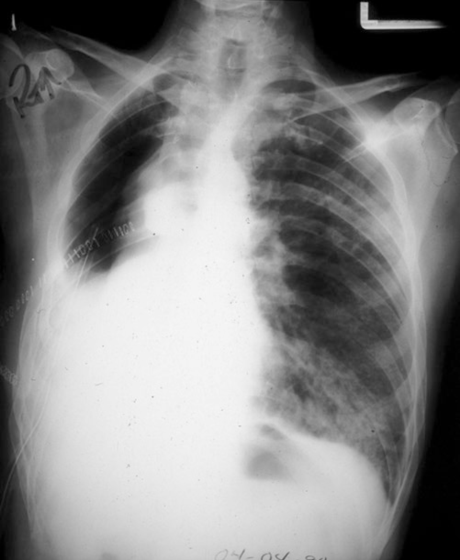

术后第3天,呼吸困难

吸空气时SpO2 85% ,氧气面罩 FiO2 0.4 时SpO2 93%

窦速104次/分,血压130/80mmHg

病人发生了什么❓❓❓

ARDS:氧合指数=动脉血氧分压( PaO2 )/吸氧浓度( FiO2);轻度(mild)<300mmHg, 中度(moderate)<200mmHg, and 重度(severe )<100mmHg),并且影像学有肺水肿表现,且肺动脉楔压(PCWP )<18 mmHg

主要表现:低氧血症,呼吸困难(影像学表现常常早于临床症状)

本例患者双肺和单肺通气潮气量设定都是700mL, 属于10ml/kg大潮气量通气,且长时间(3h)高浓度氧吸入(FiO2=1.0)是造成肺损伤的原因之一,加之中下肺叶切除术后肺功能已经损失38%,这可能是术后低氧血症的重要原因。